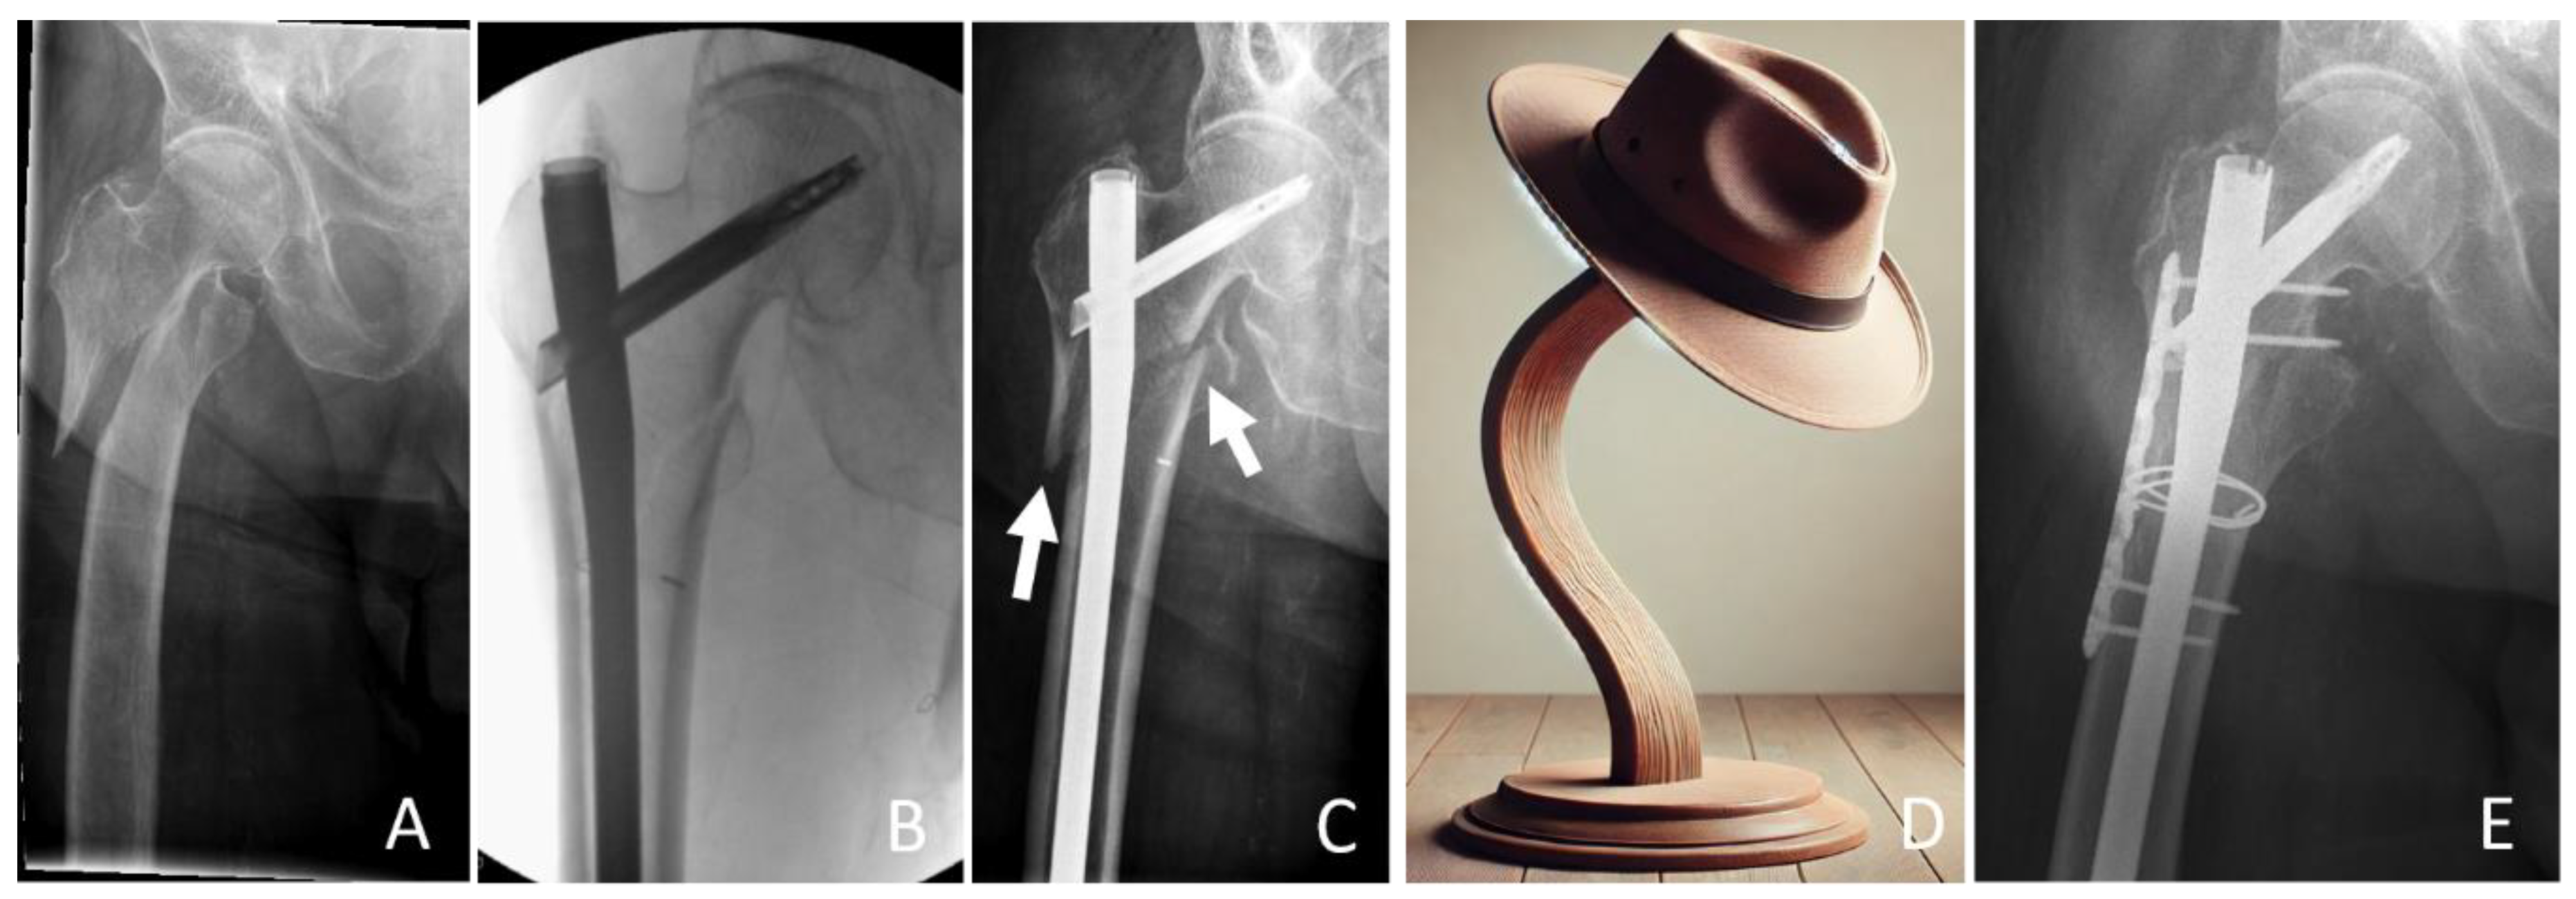

- Only for Figure 1D was AI (ChatGPT) used to produce the image. AI was not further used in the processing process of this work. Neither in the literature research process nor in the writing or processing process of this manuscript was AI used.

5.3. Reconstruction With or Without Additional Cables and Plates

5.5. Long Cephalomedullary Nail vs. Short Cephalomedullary Nail

- Zirngibl, B.; Biber, R.; Bail, H.J. How to prevent cut-out and cut-through in biaxial proximal femoral nails: Is there anything beyond lag screw positioning and tip-apex distance? Int. Orthop. 2013, 37, 1363–1368. [Google Scholar] [CrossRef][Green Version]

- Dietze, C.; Brand, A.; Friederichs, J.; Stuby, F.; Schneidmueller, D.; von Rüden, C. Results of revision intramedullary nailing with and without auxillary plate in aseptic trochanteric and subtrochanteric nonunion. Eur. J. Trauma Emerg. Surg. 2022, 48, 1905–1911. [Google Scholar] [CrossRef] [PubMed]